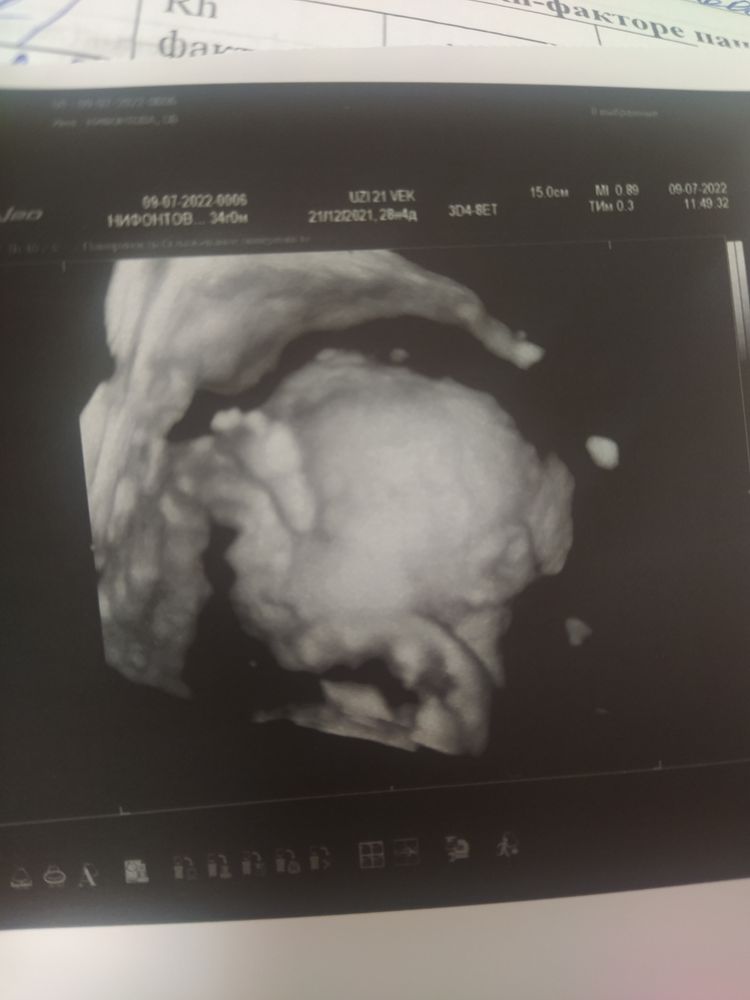

5. Спала малышка, никак ее не растормошить было. Кое как удалось заснять часть лица, а глаза рукой закрывала😊